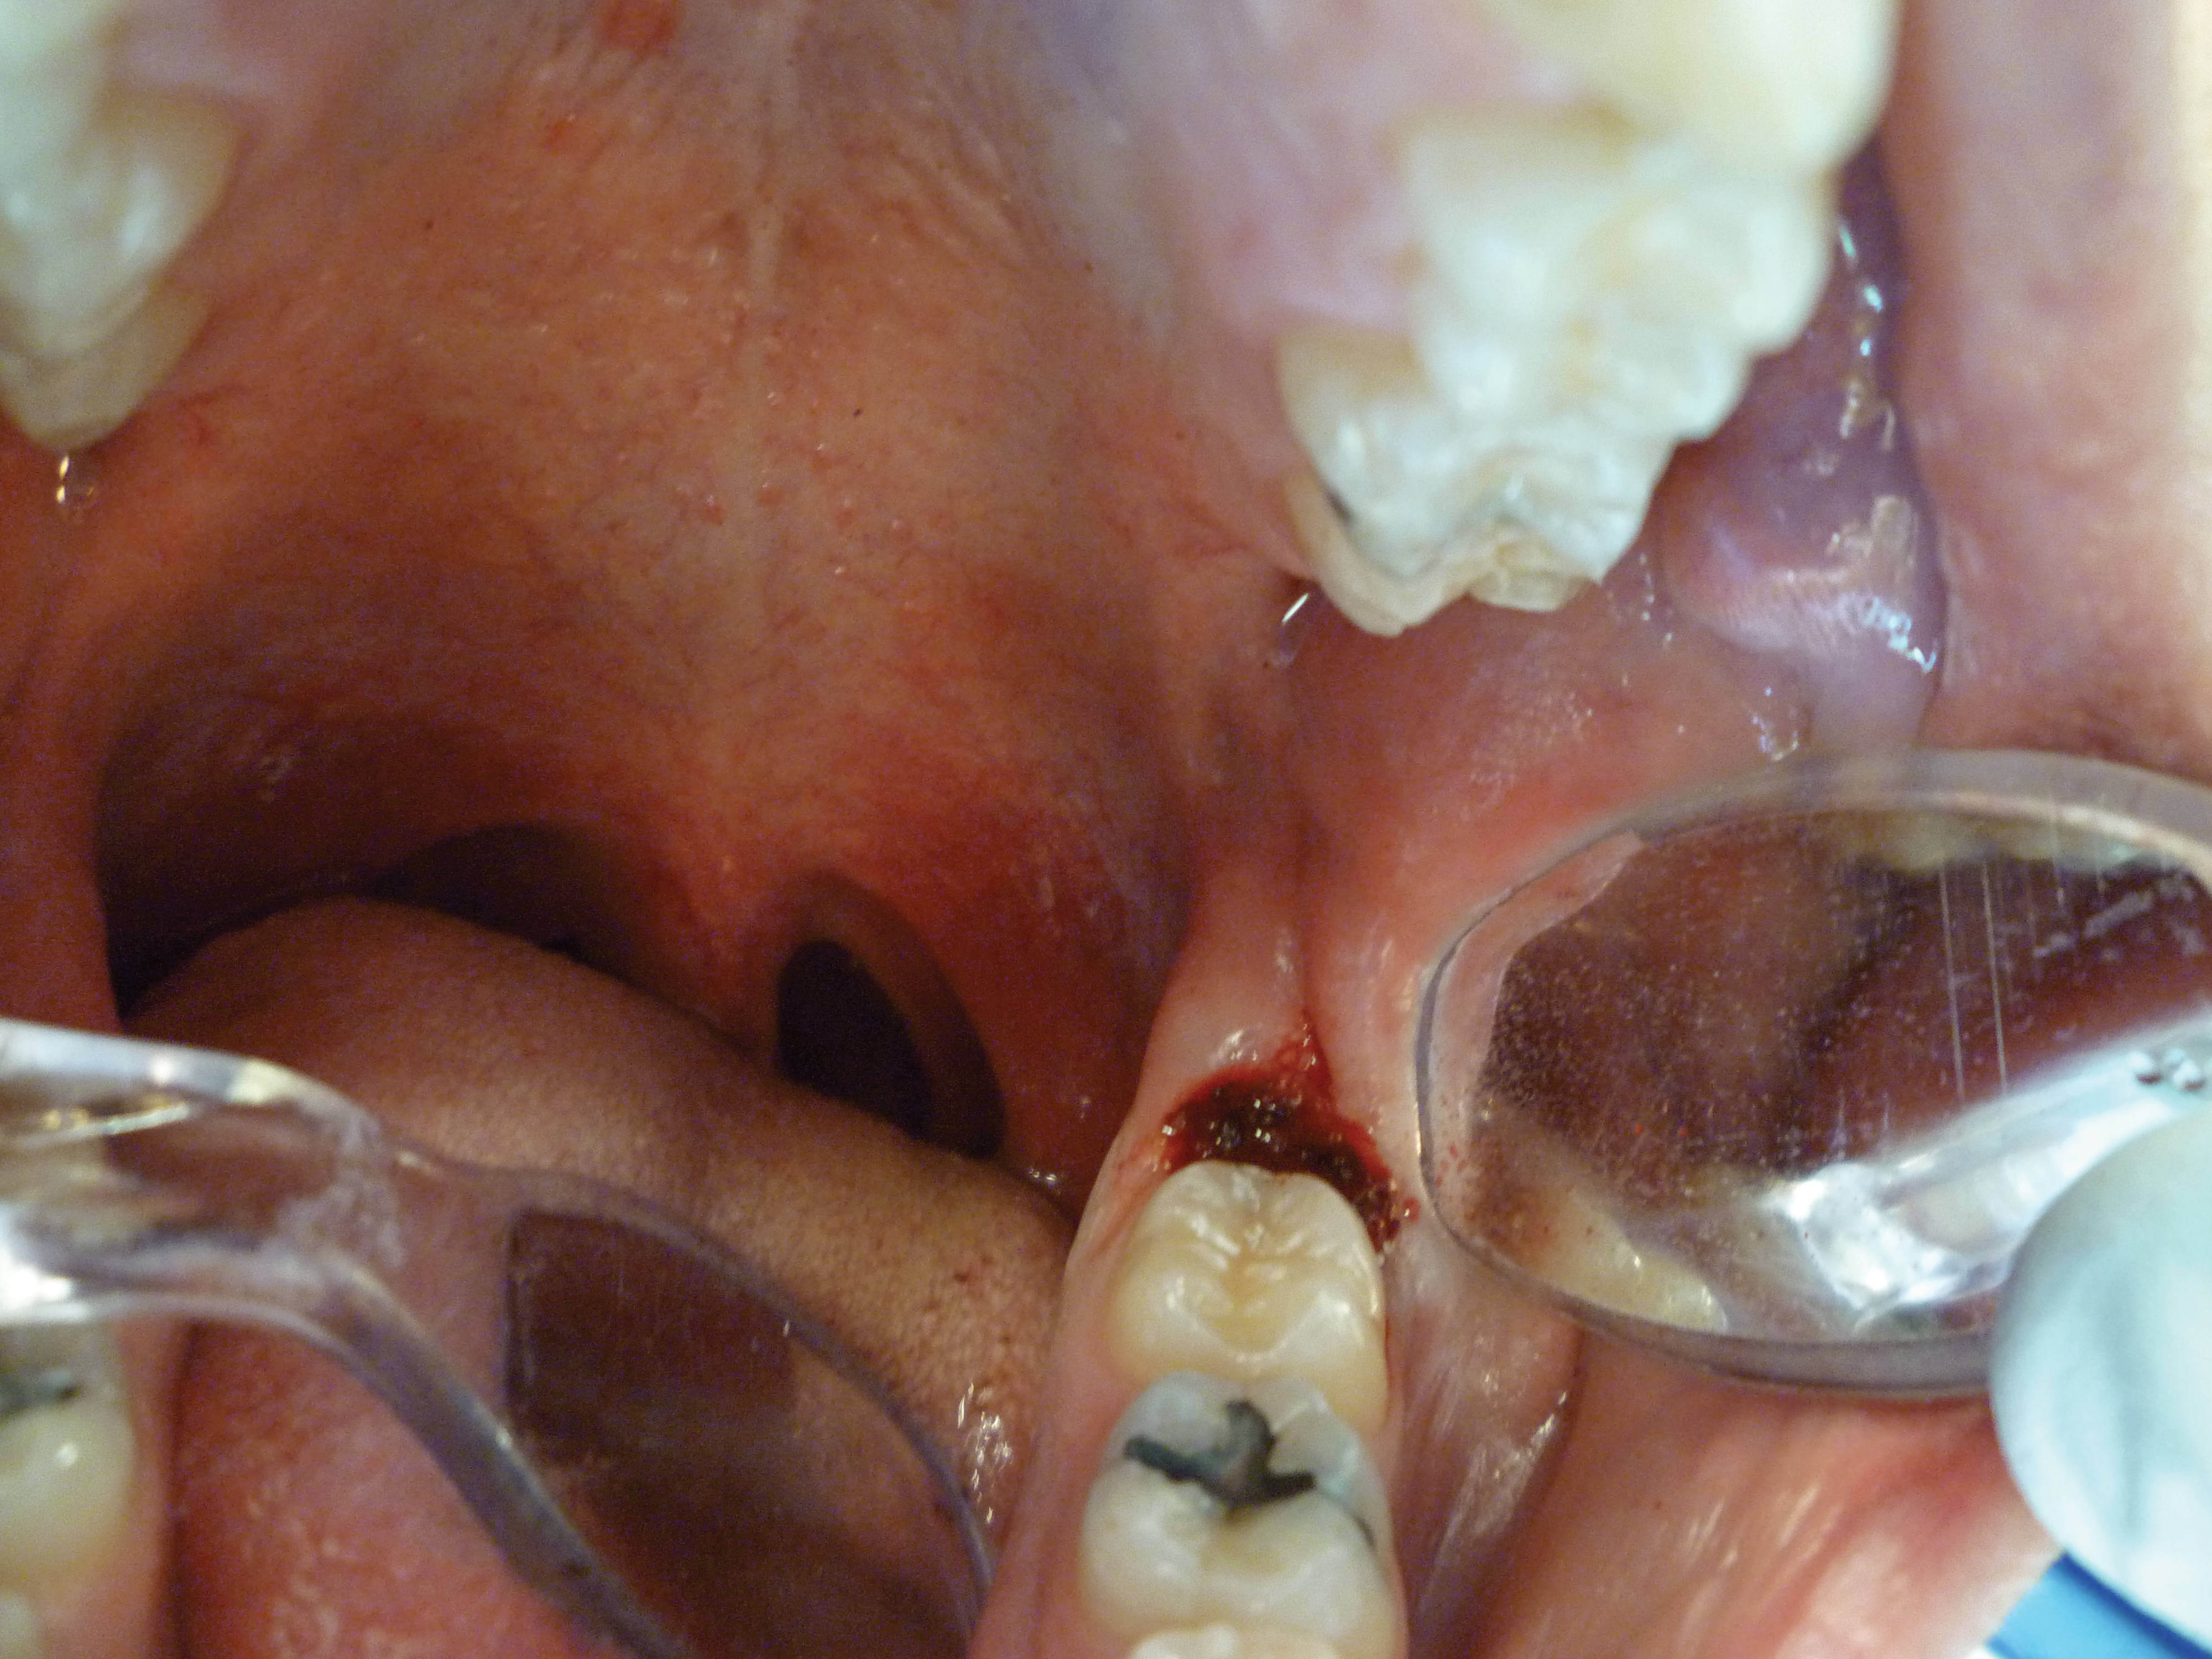

After the initial pass with the laser, the inflamed gingiva bled slightly and the surgeon defocused the beam by increasing the nozzle-to-tissue distance to quickly obtain hemostasis (Figure 6). Note the excellent visualization and the clear operatory field.

Fig 6. Excellent hemostasis after the completed ablation of the inflamed gingiva.

Figure 6